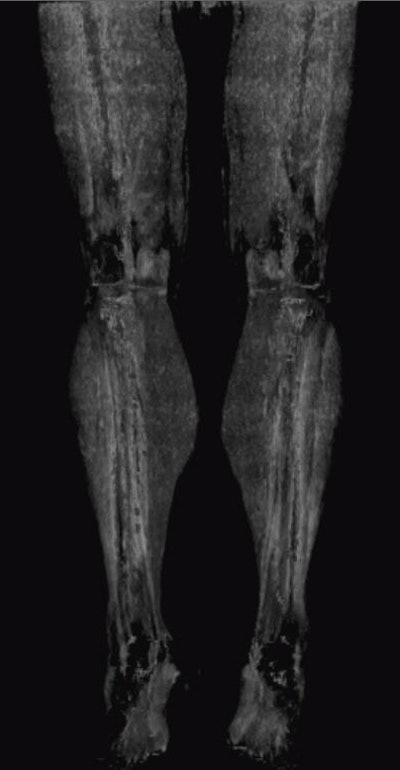

When the vessels in the lower leg are heavily calcified it's hard to tell what's going on with dynamic MRA. But acquire the images with dynamic CT, then subtract the bone, and the calcium and status of the blood flow is revealed, he said.

When the noncontrast series of images are subtracted from the bone-subtracted contrast-enhanced dynamic series, "you can finally see there is still sufficient runoff in the area of the heavy calcified plaque that is also subtracted when you subtract the complete noncontrast scan from the dynamic series," he said. And happily, the patient gets to skip the intervention.

Patient with lower-limb calcifications. Dynamic bone-subtracted dynamic CTA (below) separates the contrast from the calcifications.